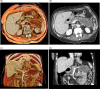

Intraductal papillary mucinous neoplasms (IPMN) of the pancreas have the potential for malignant progression into adenocarcinoma. Colloid or mucinous non-cystic carcinoma of the pancreas is an uncommon variant neoplasm that can arise within an intestinal type IPMN and have a relatively improved prognosis but may mimic the more lethal tubular or ductal adenocarcinoma. Colloid carcinoma is an infiltrating ductal epithelial neoplasm containing primarily extracellular stromal mucin pools and scant amount of centrally floating neoplastic cells. While several reports have evaluated the unique pathologic and immunohistochemical profile of colloid carcinomas, there has been limited radiologic-pathologic correlation in the literature. We report a case of an 83-year-old female who presented for evaluation of slowly progressive abdominal pain and was found to have colloid carcinoma arising from an IPMN. This is one of the first reports to correlate the multimodality radiology including cinematic rendering (CR) and histopathology features associated with this tumor. An enhanced understanding of the correlation between imaging appearance and specific histopathologic findings may aid in the early recognition and treatment of this rare neoplasm. Emphasis is placed on CR as this may help guide surgical management.